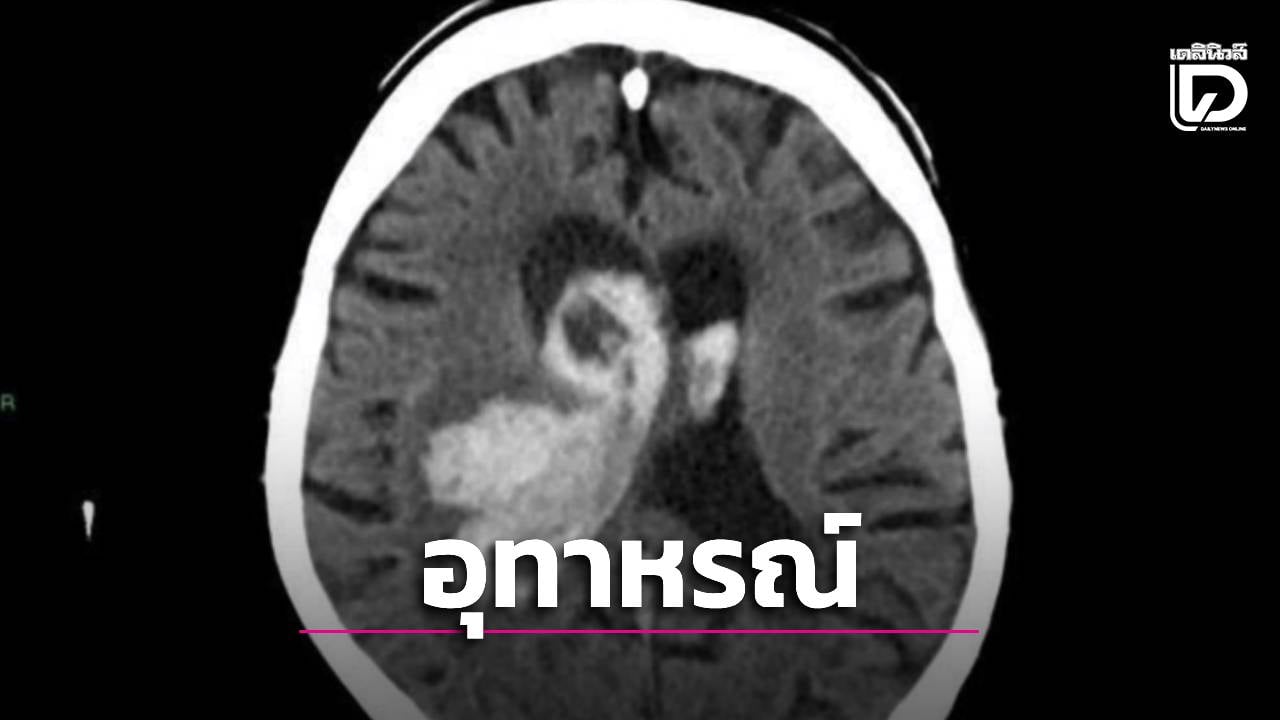

ที่ห้องฉุกเฉิน แพทย์ประเมินอย่างรวดเร็วแล้วพบว่าน่าจะเป็นโรคหลอดเลือดสมอง จึงรีบส่ง CT สมองทันที

ผลคือมีเลือดออกในใจกลางสมองส่วนที่เรียกว่า

Thalamus แถมเลือดทะลักเข้าโพรงสมอง

ซึ่งเป็นหนึ่งในตำแหน่ง ‘ขาประจำ’ ของเลือดออกในสมองจากความดันโลหิตสูง (รองจาก Basal ganglia) เพราะเป็นตำแหน่งที่หลอดเลือดได้รับแรงเฉือนสูงสุด เมื่อทุกช่วงเวลาของชีวิต ความดันอยู่ในระดับสูงตลอด มันจะค่อยๆ ทำลายผนังไปเรื่อยๆ จนเส้นใยพัง กล้ามเนื้อเรียบที่เสริมความแข็งแรงอยู่ก็พัง

ในที่สุดมันจะโป่งออกเป็นกระเปาะเล็กๆ (Charcot-Bouchard aneurysm) ซ่อนตัวอยู่ในความเงียบ รอวันที่ความดันพุ่งขึ้นมาเฉียบพลัน จะฉีกกระเปาะนี้แล้วเลือดทะลักออกมา

ซึ่งเดิมทีความดันผู้ป่วยก็สูงอยู่แล้ว ก็จะพุ่งขึ้นไปอีก ในที่สุดก็ฉีกกระเปาะที่มีไว้อยู่เดิมขาดแล้วเลือดออกท่วมสมองส่วน Thalamus ก้อนเลือดดันไปกดใยประสาทการเคลื่อนไหว (Internal capsule) ซึ่งทำให้เกิดการอ่อนแรงครึ่งซีกเฉียบพลัน